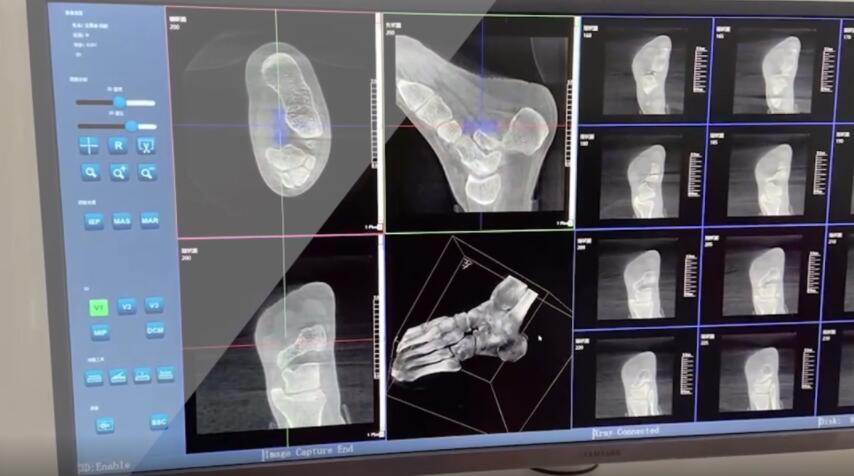

踝关节是人体中负重较大的关节,也是活动度较大的地方,所以对于足踝部位的关节内骨折,我们更需要做到“解剖复位”。对于这种关节内的骨折,尤其是踝关节内部的骨折,不仅需要进行X影像平片正侧位的拍摄,由于在二维影像上无法判断关节面的受损情况,往往还需要进行三维影像的检查。

在术前,我们需要做三维扫描的CT检查,我们必须要有CT的片子,还要有三维的重建。

在术中,我们怎么去判断关节面平不平整呢?常规的正侧位影像是不能判断的。有些医生为了准确的判断,可能会选择做开放性的手术,把关节暴露出来,在眼睛的直视下判断关节面平不平整。但是关节全部打开,无疑增加了病人的创伤,而且增加了患者的恢复时间。所以如果在术中我们有三维影像的支持,对医生做手术而言就会事半功倍,而且能够大大的增加手术准确度,增加患者术后的预后。所以在术中有三维影像的支持是非常必要的!

三维影像 看透关节内骨折的“眼睛”